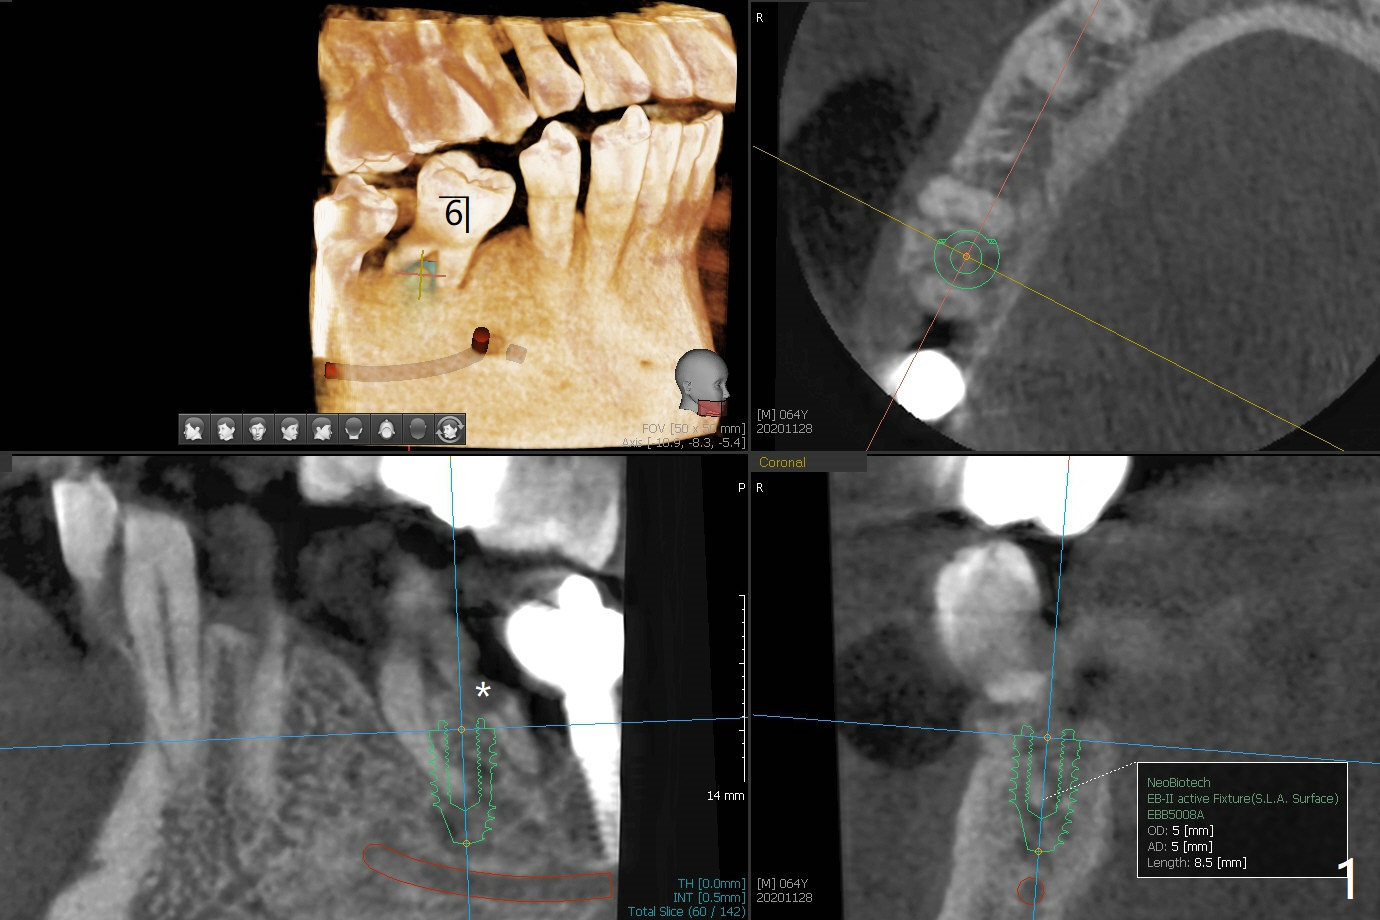

64岁男不注意口腔卫生,因为右上8颊侧颈部龋齿疼痛就诊拔除,也同意拔除右下6(远中颈部龋齿,图一:*),种植5,6(图一,二),如果扭力不是太差,即刻制作临时连冠,保护粘性骨粉,而且有利于马上提高口腔卫生(刷牙),也要求使用水牙线。伤口愈合后,牙冠分开,有利于龈乳头形成。